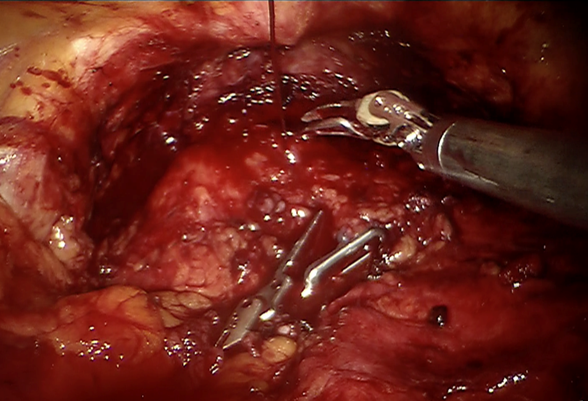

Una vez liberada la porción posterior y lateral, el adenoma se diseca meticulosamente en la porción medial, utilizando exclusivamente disección roma en este punto, tratando de preservar la uretra, lo que puede ayudar a conservar la eyaculación anterógrada. Se lleva a cabo el mismo procedimiento contralateral. (Figura 3)

Se observa lecho prostático una vez terminada la enucleación del adenoma en ambos lóbulos laterales. En la porción central se observa uretra prostática íntegra (flecha). La tracción de la sonda transuretral permite una mejor referencia el sitio de la uretra. La hemostasia se realiza con agentes hemostáticos, aunado a sutura hemostática y energía monopolar y bipolar estando alejado a la uretra.

Figura 3 Lecho prostático una vez terminada la enucleación del adenoma en ambos lóbulos laterales